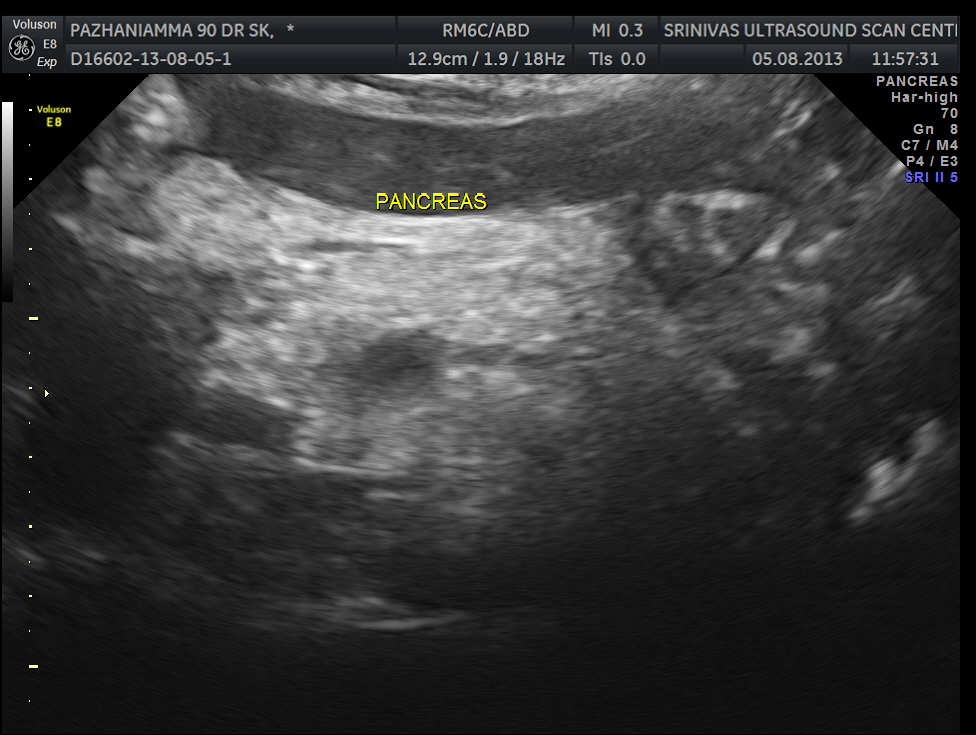

pancreas, spleen and both kidneys were normal.